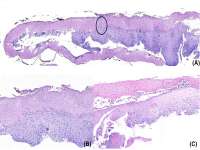

王功伟老师肾脏肿瘤系列讲座(十五):

王功伟

北京大学人民医院病理科